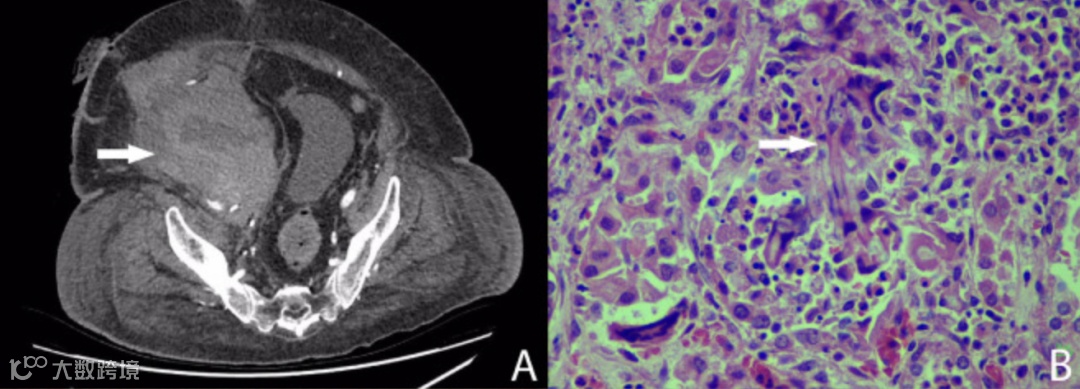

第22天,患者再次出现低血压。CT血管造影显示肾动脉和髂外动脉吻合口处有活动性出血(图A);患者接受经皮支架植入术,血液外渗得以解决。

移植物的组织病理学显示为肿大、苍白肾脏,有几个直径达5毫米的白斑。显微镜检查显示炎症区域含有嗜中性粒细胞和多核巨细胞,包围真菌菌丝和分生孢子(图B)。荧光原位杂交的真菌筛查呈阳性,酵母菌筛查呈阴性。肾动脉、肾静脉、肾盂和输尿管未发现真菌。然而,肾动脉样本培养呈黄曲霉菌(Aspergillus flavus)阳性。患者开始口服伏立康唑(400mg Bid负荷剂量,随后200mg Bid),并在第31天接受进一步手术,以移除支架和供体主动脉补片,随后的支架和补片培养均为黄曲霉菌和万古霉素耐药肠球菌(VRE)阳性。为了保护右腿的动脉供应,接受股-股旁路手术。加入利奈唑胺以覆盖VRE,伏立康唑改为静脉给药,并进行治疗药物监测。